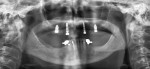

The zirconia implant bridge was seated in the patient’s mouth, and periapical films confirmed proper fit. Panorex radiographs demonstrated anatomical structures (Figure 12 and Figure 13). The crown and zirconia implant bridge screw access hole was filled with polyvinyl siloxane material (Figure 14). The crown was temporarily cemented in place using transparent temporary cement (Teliolink, Ivoclar Vivadent) while the abutment screws were torqued to 35 Ncm and covered with flowable composite (Tetric EvoFlow, Ivoclar Vivadent) (Figure 15). The composite was then light-cured (Demetron, Kerr Corporation, www.kerrdental.com).